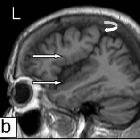

Bilateral

symmetrical perisylvian polymicrogyria.. Sagittal (a,b) and coronal (c) T1-weighted images show that polymicrogyria involves the entire perisylvian cortex (arrows) and extents posteriorly to the central sulcus (curved arrows).